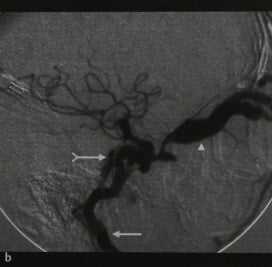

Кортикокавернозная фистула. ЦСА, заднепередняя (а) и латеральная проекции (b). Фаза раннего артериального наполнения (ВСА - стрелка) кавернозного синуса (раздвоенная стрелка), дренирующегося в оба каменистых синуса. Расширенная верхняя глазная вена (наконечник стрелки).

5. Ангиография при травматической каротидно-каверной фистуле:

• Традиционная:

о Раннее заполнение контрастом КС + путей оттока, включая:

- Ретроградное заполнение контрастом ВГВ, угловых + лицевых вен

- Контралатеральный КС

- Каменистые синусы → внутреннюю яремную вену(ы)

о Снижение или отсутствие антеградного кровотока во ВСА за пределами фистулы, зависит от размера дефекта ВСА

(б) ЦСА, боковая проекция: у пациента с ККФ в артериальную фазу определяется контрастирование пещеристого синуса. Также контрастированы множественные венозные пути оттока крови из пещеристого синуса, включая верхние глазные вены, верхний и нижний каменистые синусы, крыловидное и глоточное венозные сплетения.